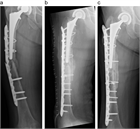

1. ⼈⼯股関節置換術(total hip arthroplasty、THA)後⾻折は種々の外⼒により発⽣するが、minor traumaによるものが多く、その発生率は一次THA後で約3.5%と報告されており、THA施行数の増加に伴い今後さらに増加すると予測される。

1. ステムの固定性が良好である場合は、ロッキングプレート、Dall-Miles cable grip system、ワイヤー、スクリューを用いた骨接合術が推奨される(推奨度1)

1. ステムに弛みを認める場合は、再置換術と骨接合術を行う(推奨度1)